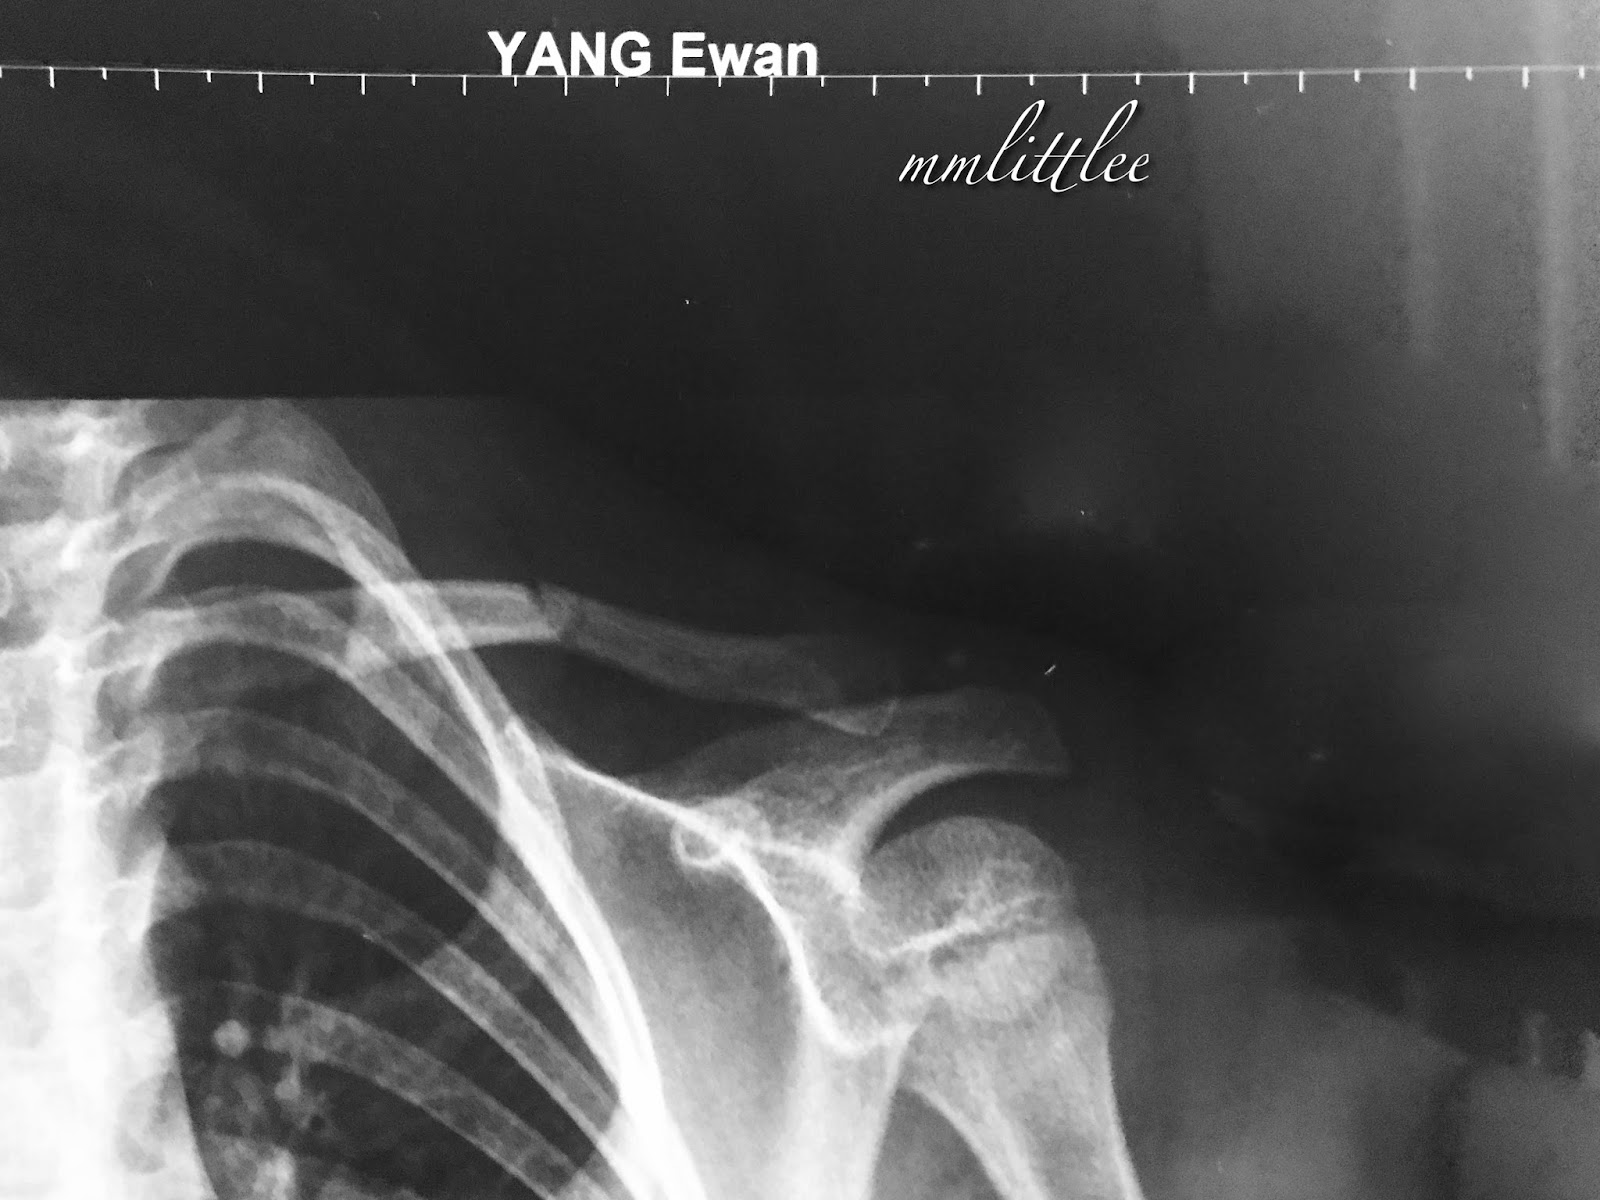

From mmlittlee.blogspot.com

Ewan's Fractured Collarbone Does A Collarbone Fracture Hurt A clavicle fracture can be very painful and may make it hard to move your arm. Some people also experience discomfort in the fracture site during colder weather. Your local pharmacy can give you advice on managing pain after a fracture. You might see or feel a bump where the bone is. it’s normal to have some pain even. Does A Collarbone Fracture Hurt.